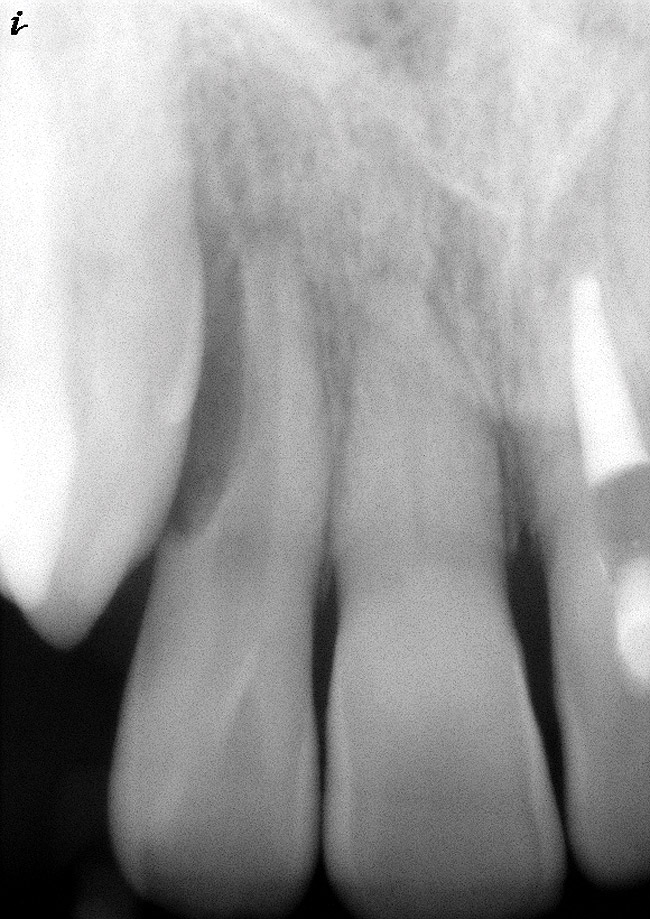

As mentioned, all risk factors associated with both root canal and implant therapy must be carefully considered. Comprehensive clinical and radiographic assessments are necessary to evaluate the patient's risk factors associated with his or her particular case (Figure 1, Figure 2 and Figure 3). The primary risk factors for implants can include smoking, bone quality, and systemic health. For endodontic therapy the primary risk factors are related to the anatomic root complexity, failed root canal treatment with significant technical defects manifested as iatrogenic events, less-than-optimal periodontal status of the tooth (due to a subsequent risk of vertical fracture), and a clinician's lack of experience with regard to the case's complexity. A strong correlation exists between failed root canal treatment and a lack of coronal seal after treatment. This is highly relevant in treatment planning. Often, endodontically treated teeth fail not because they were treated inappropriately and need extraction, but rather, because they have been left unsealed and assaulted by bacteria after the endodontic therapy, causing subsequent long-term clinical failure (Figure 4 and Figure 5).